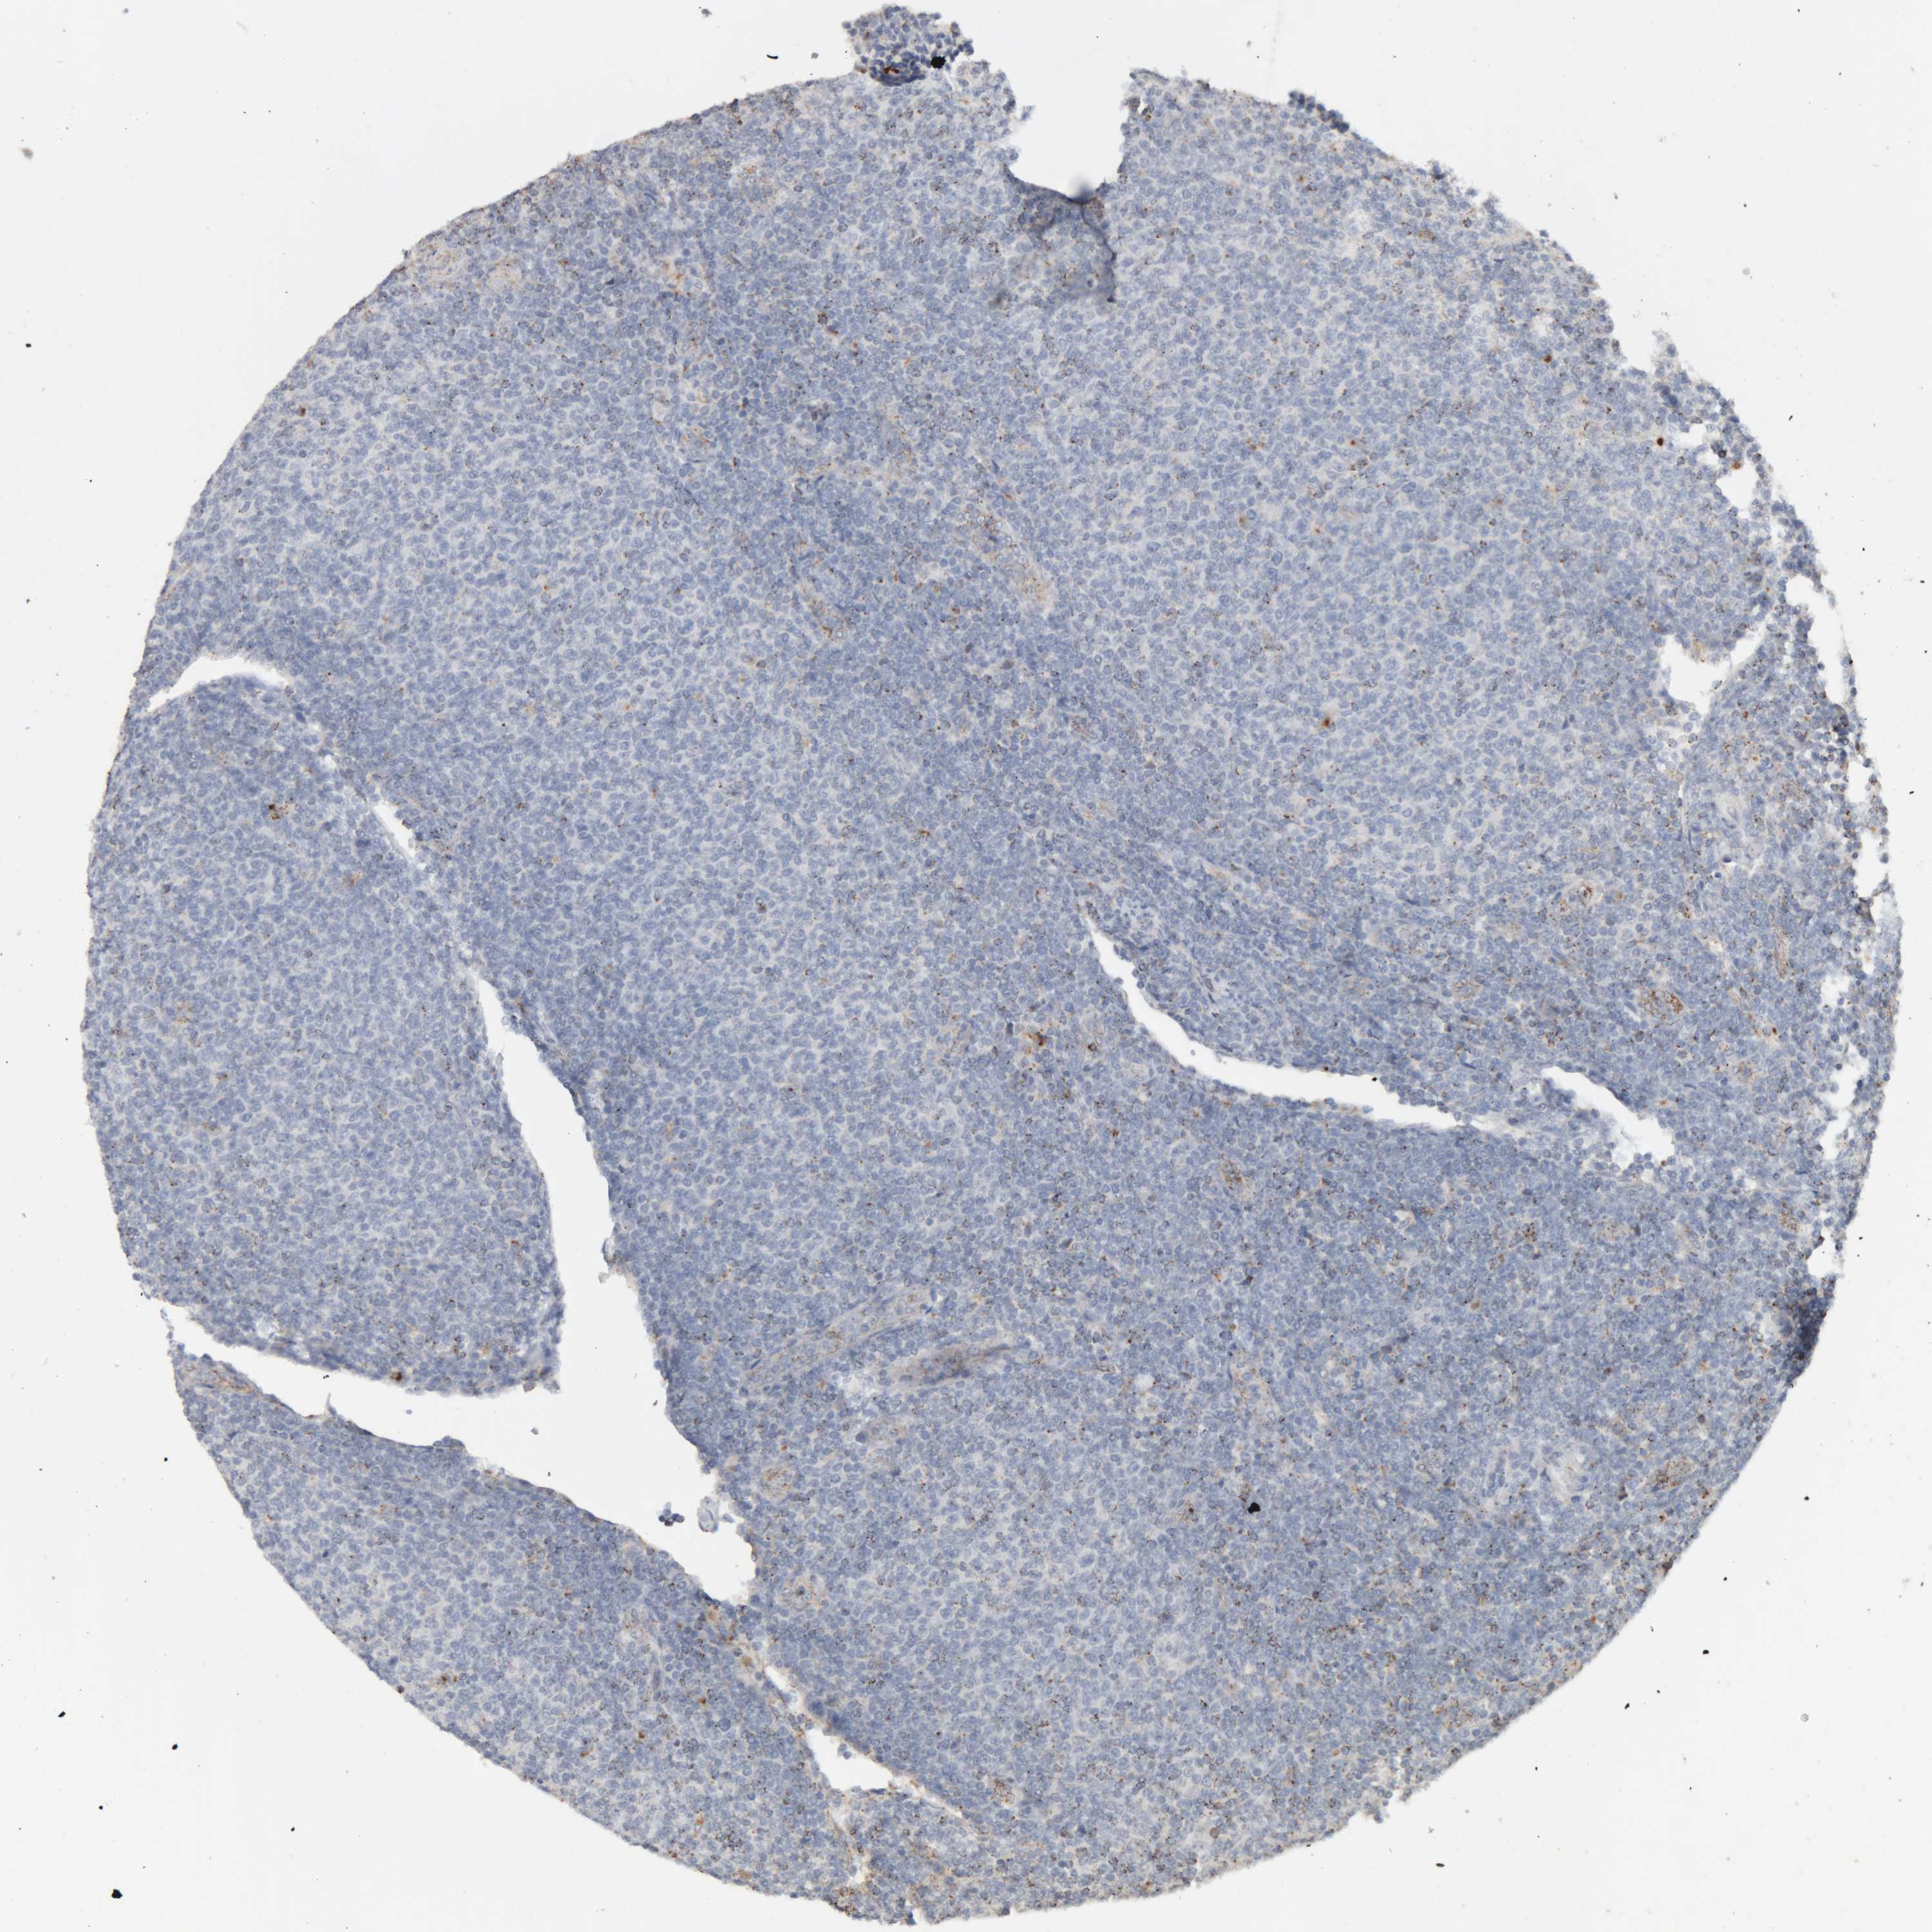

CANCER LYMPHOMA Show tissue menu

LYMPHOMA - Protein expressioni

A mouse-over function shows sample information and annotation data. Click on an image to view it in a full screen mode. Samples can be filtered based on level of antibody staining by selecting one or several of the following categories: high, medium, low and not detected. The assay and annotation is described here.

Antibody stainingi

Antibody staining in the annotated cell types in the current human tissue is reported as not detected, low, medium, or high, based on conventional immunohistochemistry profiling in selected tissues. This score is based on the combination of the staining intensity and fraction of stained cells.

Each image is clickable and will lead to virtual microscopy that enables deeper exploration of all samples and also displays staining intensity scores, fraction scores and subcellular localization as well as patient and tissue information for each sample.

Antibody HPA005554

Antibody CAB025183

Staining

High

Medium

Low

Not detected

Intensity

Strong

Moderate

Weak

Negative

Quantity

>75%

75%-25%

<25%

None

Location

Nuclear

Cytoplasmic/membranous

Cytoplasmic/membranous,nuclear

Malignant lymphoma, non-Hodgkin's type, High grade

Malignant lymphoma, non-Hodgkin's type, Low grade